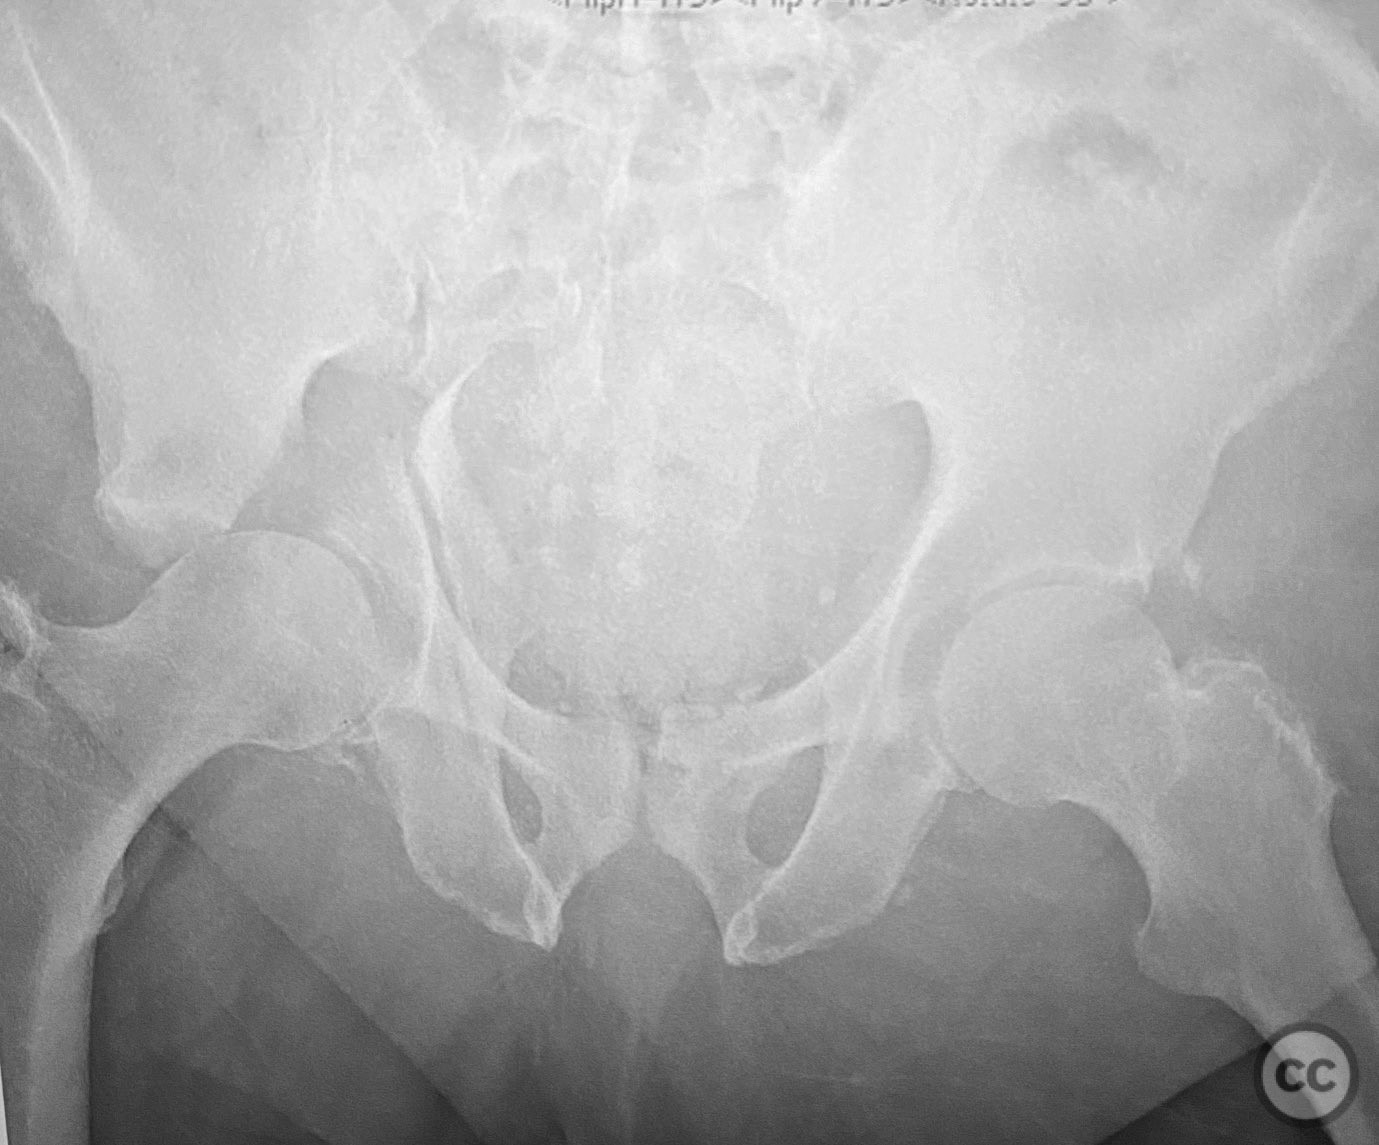

Associated both column acetabular fractu...

Seattle, United States

Pelvis - AO/OTA 6x

Associated both-column acetabular fractu...

Schleswig Holstein, Germany

Geriatric Polytrauma - ipsilateral aceta...

, United States